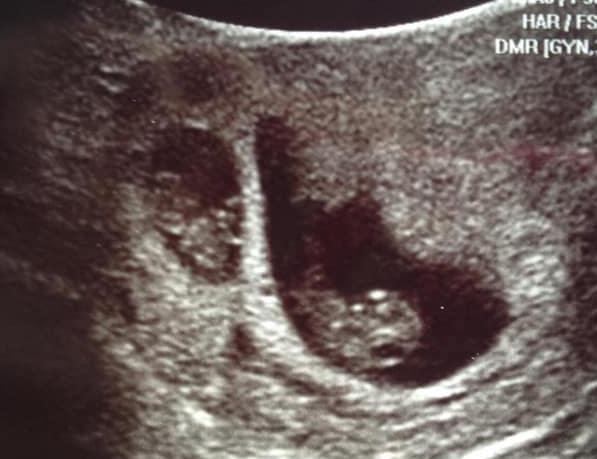

Early Twin Ultrasound at 7 Weeks

The earliest your doctor would likely order an ultrasound confirming twins would be 4 weeks pregnant. But unless you are going through fertility treatments, doing an ultrasound before 6 weeks isn’t very common, with the exception of complications. Women who are going through fertility treatments or have early complications may be able to have an early twin ultrasound at 4 or 5 weeks pregnant and find out they are pregnant with twins.

At four to five weeks after a pregnant woman’s last period the ultrasound commonly shows a small collection of fluid within the lining of the uterus that represents the early development of the gestational sac. At about five and a half weeks after a pregnant woman’s last period the ultrasound typically shows a gestational sac and within it we can see a 3-5 mm bubble-like structure, which is the yolk sac. At approximately six weeks after a pregnant woman’s last period, we can see a small fetal pole, one of the first stages of growth for an embryo, which develops alongside the yolk sac.

Yes! You’d need to have an ultrasound at 7 weeks to confirm a twin pregnancy. Your twin belly at 7 weeks may not look like much of a belly at all, so getting in to your doctor for an ultrasound is key to find out if you’re really having twins.